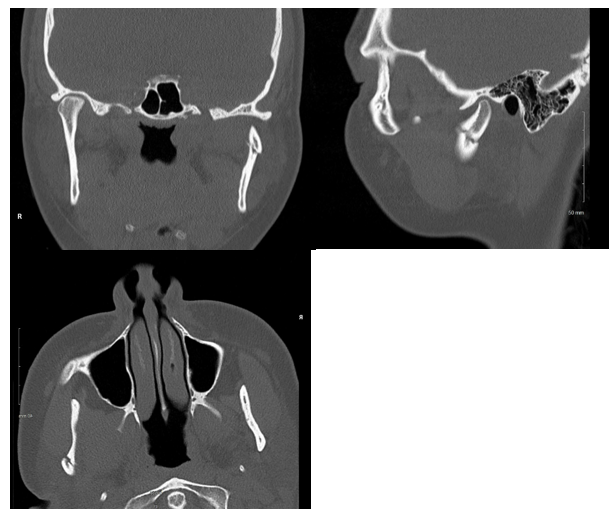

A healthy, non-smoking, 22-year-old woman presented to the emergency department after suffering a fall from her bicycle. She was helmeted and denied any loss of consciousness or neck symptoms. Lower lip and chin lacerations were evident and she reported that her bite did not align. A noncontrast maxillofacial CT was obtained and showed a minimally displaced fracture of the right mandibular body and a minimally displaced fracture of the left mandibular condyle (Figures 1 & 2). Her soft tissues injuries were repaired and she was referred to the otolaryngology clinic for management of her fractures. Two days following the injury, the patient was evaluated in the clinic. She reported pain throughout the mandible in addition to trismus and mild malocclusion. The fractures were discussed and surgical treatment with ORIF and MMF was advised. An informed consent discussion occurred in which the risks and benefits of both the recommended treatment and no treatment were made clear. The patient expressed reasonable reservations about the surgery and opted for non-surgical management only. She was warned of the risks of non-union, malunion, and a potentially prolonged recovery period. Given her choice, she was strongly advised to visit the clinic on a weekly basis, adhere to a slowly progressing diet, and otherwise rest her jaw. The patient presented as mature and reliable and agreed to the plan.

Figure 1 Non-contrast CT. Left to right, top to bottom; coronal, sagittal, and transverse views of the right mandibular body fracture.